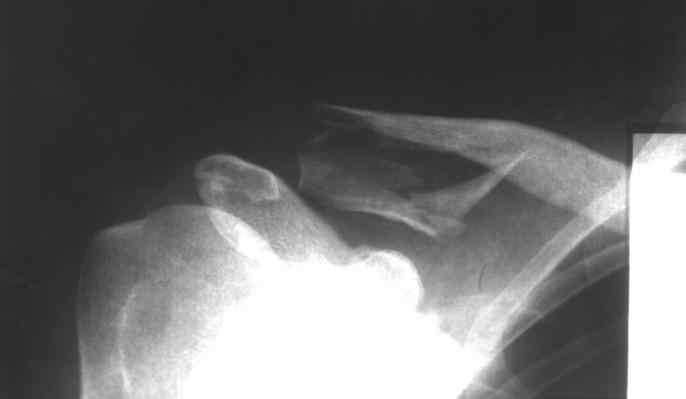

[Ortho] Оскольчатый перелом ключицы

Пациент,32 года, травма - падение с высоты на правое плечо. Прооперирован 20.05.08....

Ad oculus, при ревизии перелома, многооскольчатый перелом, акромеально-ключичное

сочленение сохранено. Коллеги, прошу высказать ваше мнение по поводу данного случая: Выбор

метода? качество остеосинтеза? ваш вариант лечения? Возможные осложнения? Спасибо!